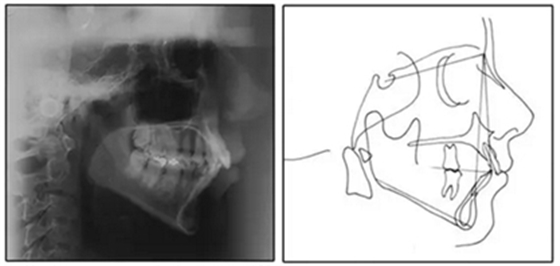

患者是一名39歲的白人婦女,病史不明。她主訴是她的右側(cè)顳下關(guān)節(jié)有不適癥狀,并希望改善她的笑容。她有一個(gè)對(duì)稱的臉型和一個(gè)II類2分類的微笑。她的側(cè)貌是凸的,90°的鼻唇角和骨性下頜骨發(fā)育不足??趦?nèi),上頜中線與面部重合,但下頜中線向右側(cè)偏移5mm;存在6mm的深覆蓋。她的兩側(cè)都是I類磨牙關(guān)系,左側(cè)是I類尖牙關(guān)系,右側(cè)是完全的II類尖牙關(guān)系。下頜右側(cè)第二前磨牙先天性缺失(圖1和圖2)。最初的全景片顯示了足夠的骨質(zhì)水平和全部的第三磨牙(圖3)。治療前的頭影測(cè)量片片和相應(yīng)的頭影測(cè)量圖(圖3)證實(shí)ANB為7°,Wits評(píng)估為6 mm的骨性II類錯(cuò)合(表)。上頜切牙相對(duì)與面部和顱底的位置很好。下頜切牙前傾。診斷為II類2分類錯(cuò)合畸形,伴有骨性下頜發(fā)育不足,右側(cè)顳下頜關(guān)節(jié)癥狀,下頜中線向右側(cè)偏移5mm,先天性右下第二前磨牙缺失。

圖3. 治療前頭影側(cè)位片,頭影測(cè)量描跡圖和全口X光片